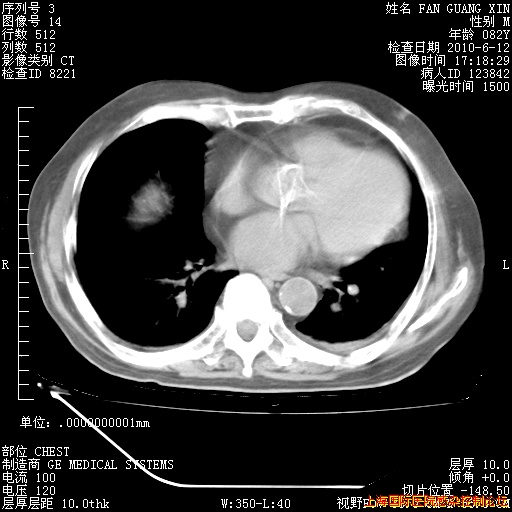

6月12日纵膈窗